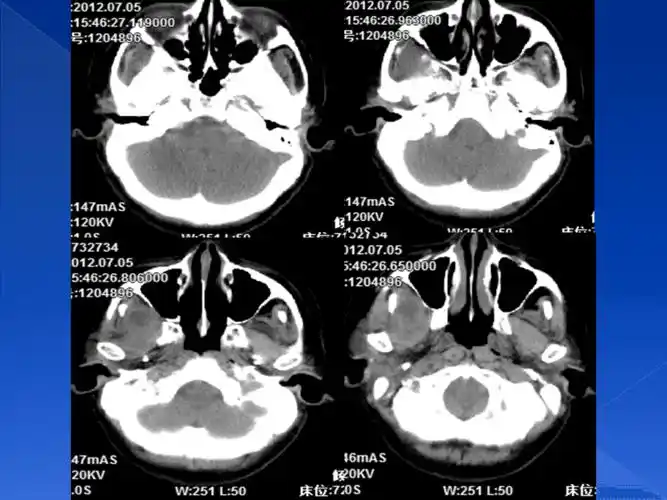

ct示:颅底凹陷